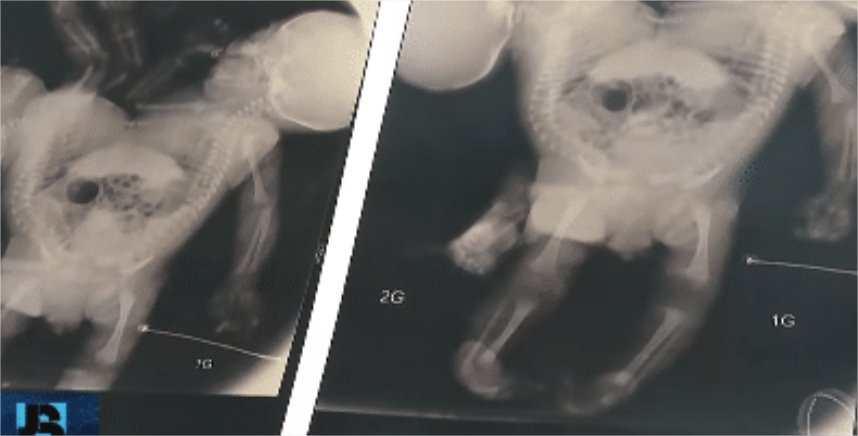

Os recém-nascidos são classificados como isquiópagos, unidos pelo tórax, abdômen, bacia e pernas. “O fígado é único, a bacia também é única, nós não sabemos ainda como é que é a parte urinária da bexiga, se elas são unidas, separadas”, explicou, ao Jornal da Record, o médico Zacarias Calil, que já atuou no parto de 46 bebês siameses e na separação de 25.

Nos próximos dias, os irmãos passarão por uma nova intervenção cirúrgica para corrigir uma má formação no intestino. A complexidade da futura separação exige um longo período de preparo. “A cirurgia de separação dos gêmeos pode acontecer daqui um ano, de acordo com os médicos, dependendo do desenvolvimento das crianças”, informou o hospital.